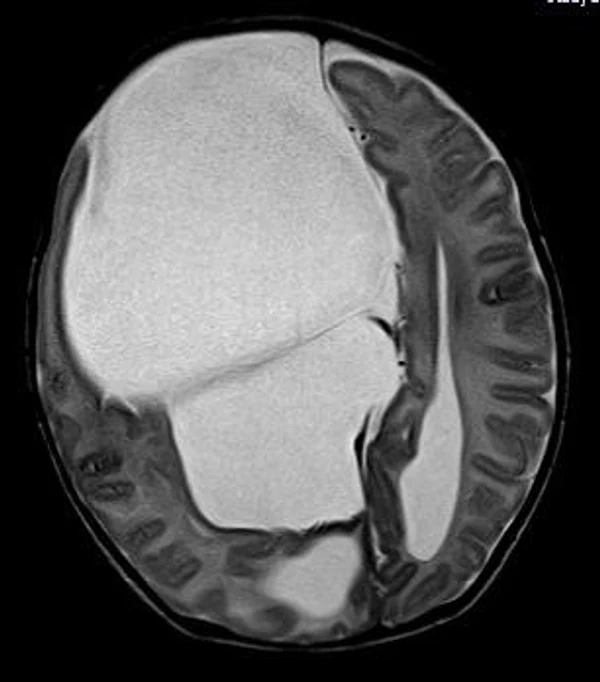

кисты, аномалии Денди-Уокера и др.Операции при внутричерепных кистах. В основном встречаются арахноидальные кисты различных локализаций и кисты сосудистых сплетений боковых желудочков. Пациентам с врождёнными кистами операции проводятся в следующих ситуациях: увеличении объема кисты в динамике, наличии клинических проявлений, компрессии и дислокации мозговых структур, наличии окклюзии ликворных путей. Нами используются 2 способа хирургического лечения кист: эндоскопическая перфорация стенок кист и открытая резекция кист. Открытая резекция кист проводится при ретроцеребеллярных арахноидальных кистах (рис. 2), при арахноидальных кистах межполушарной щели при отсутствии непосредственного контакта их стенок со стенками расширенных желудочков головного мозга и повторного увеличения кист средней черепной ямки после эндоскопической кисто-цистерностомии. Техника операции заключается в проведение краниотомии и максимальном иссечении стенок кист с созданием широкого сообщения кист с субарахноидальным пространством. Эндоскопические операции проводятся при арахноидальных кистах межножковой и пинеальной цистерн, арахноидальных кистах межполушарной щели при тесном контакте их стенок со стенками расширенной желудочковой системы (рис. 3), первично при арахноидальных кистах средней черепной ямки, а также при кистах сосудистых сплетений боковых желудочков. При арахноидальных кистах межножковой цистерны эндоскопически проводится перфорация стенок кисты, сообщая ее с просветом III желудочка и межножковой цистерной – эндоскопическая вентрикуло-кисто-цистерностомия (рис. 4). При арахноидальных кистах пинеальной цистерны проводится перфорация кисты в передне-верхних её отделах с созданием сообщения полости кисты с просветом III желудочка – эндоскопическая кисто-вентрикулостомия. С целью предотвращения облитерации сформированного отверстия иногда в полость кисты под контролем эндоскопа вводится стент перфорированный на протяжении (рис. 5, 6). Эндоскопическая кисто-цистерностомия выполняется при арахноидальных кистах средней черепной ямки. При этом создается широкое сообщение кисты с базальными цистернами. При кистах сосудистых сплетений боковых желудочков проводится их вскрытие в просвет боковых желудочков – эндоскопическая кисто-вентрикулостомия. При множественных кистах проводится их хирургическое сообщение между собой – интеркистосмия